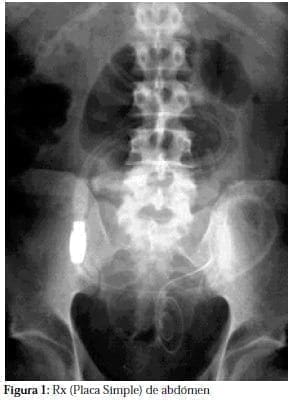

Una radiografía simple de abdomen (figura 1), cistografía (figura 2), las cuales mostraban la porción distal del catéter en la pelvis menor, así mismo se realizó urotac (figura 3a y b) que confirma la presencia del catéter en la vejiga.

La uropatia neurogénica que conlleva a vejigas atónicas o hipotónicas se asocia con diabetes de larga evolución. La placa de abdomen simple se puede considerar diagnostica, tanto en la posición antero posterior como oblicua, la porción distal del catéter entorchado, se encuentra en posición suprapúbica y sobre la silueta vesical y muy por debajo del repliegue peritoneal inferior, hallazgos que se confirmaron mediante Urotac y uretrocistoscopia, previos la corrección quirúrgica y reacomodación del catéter.